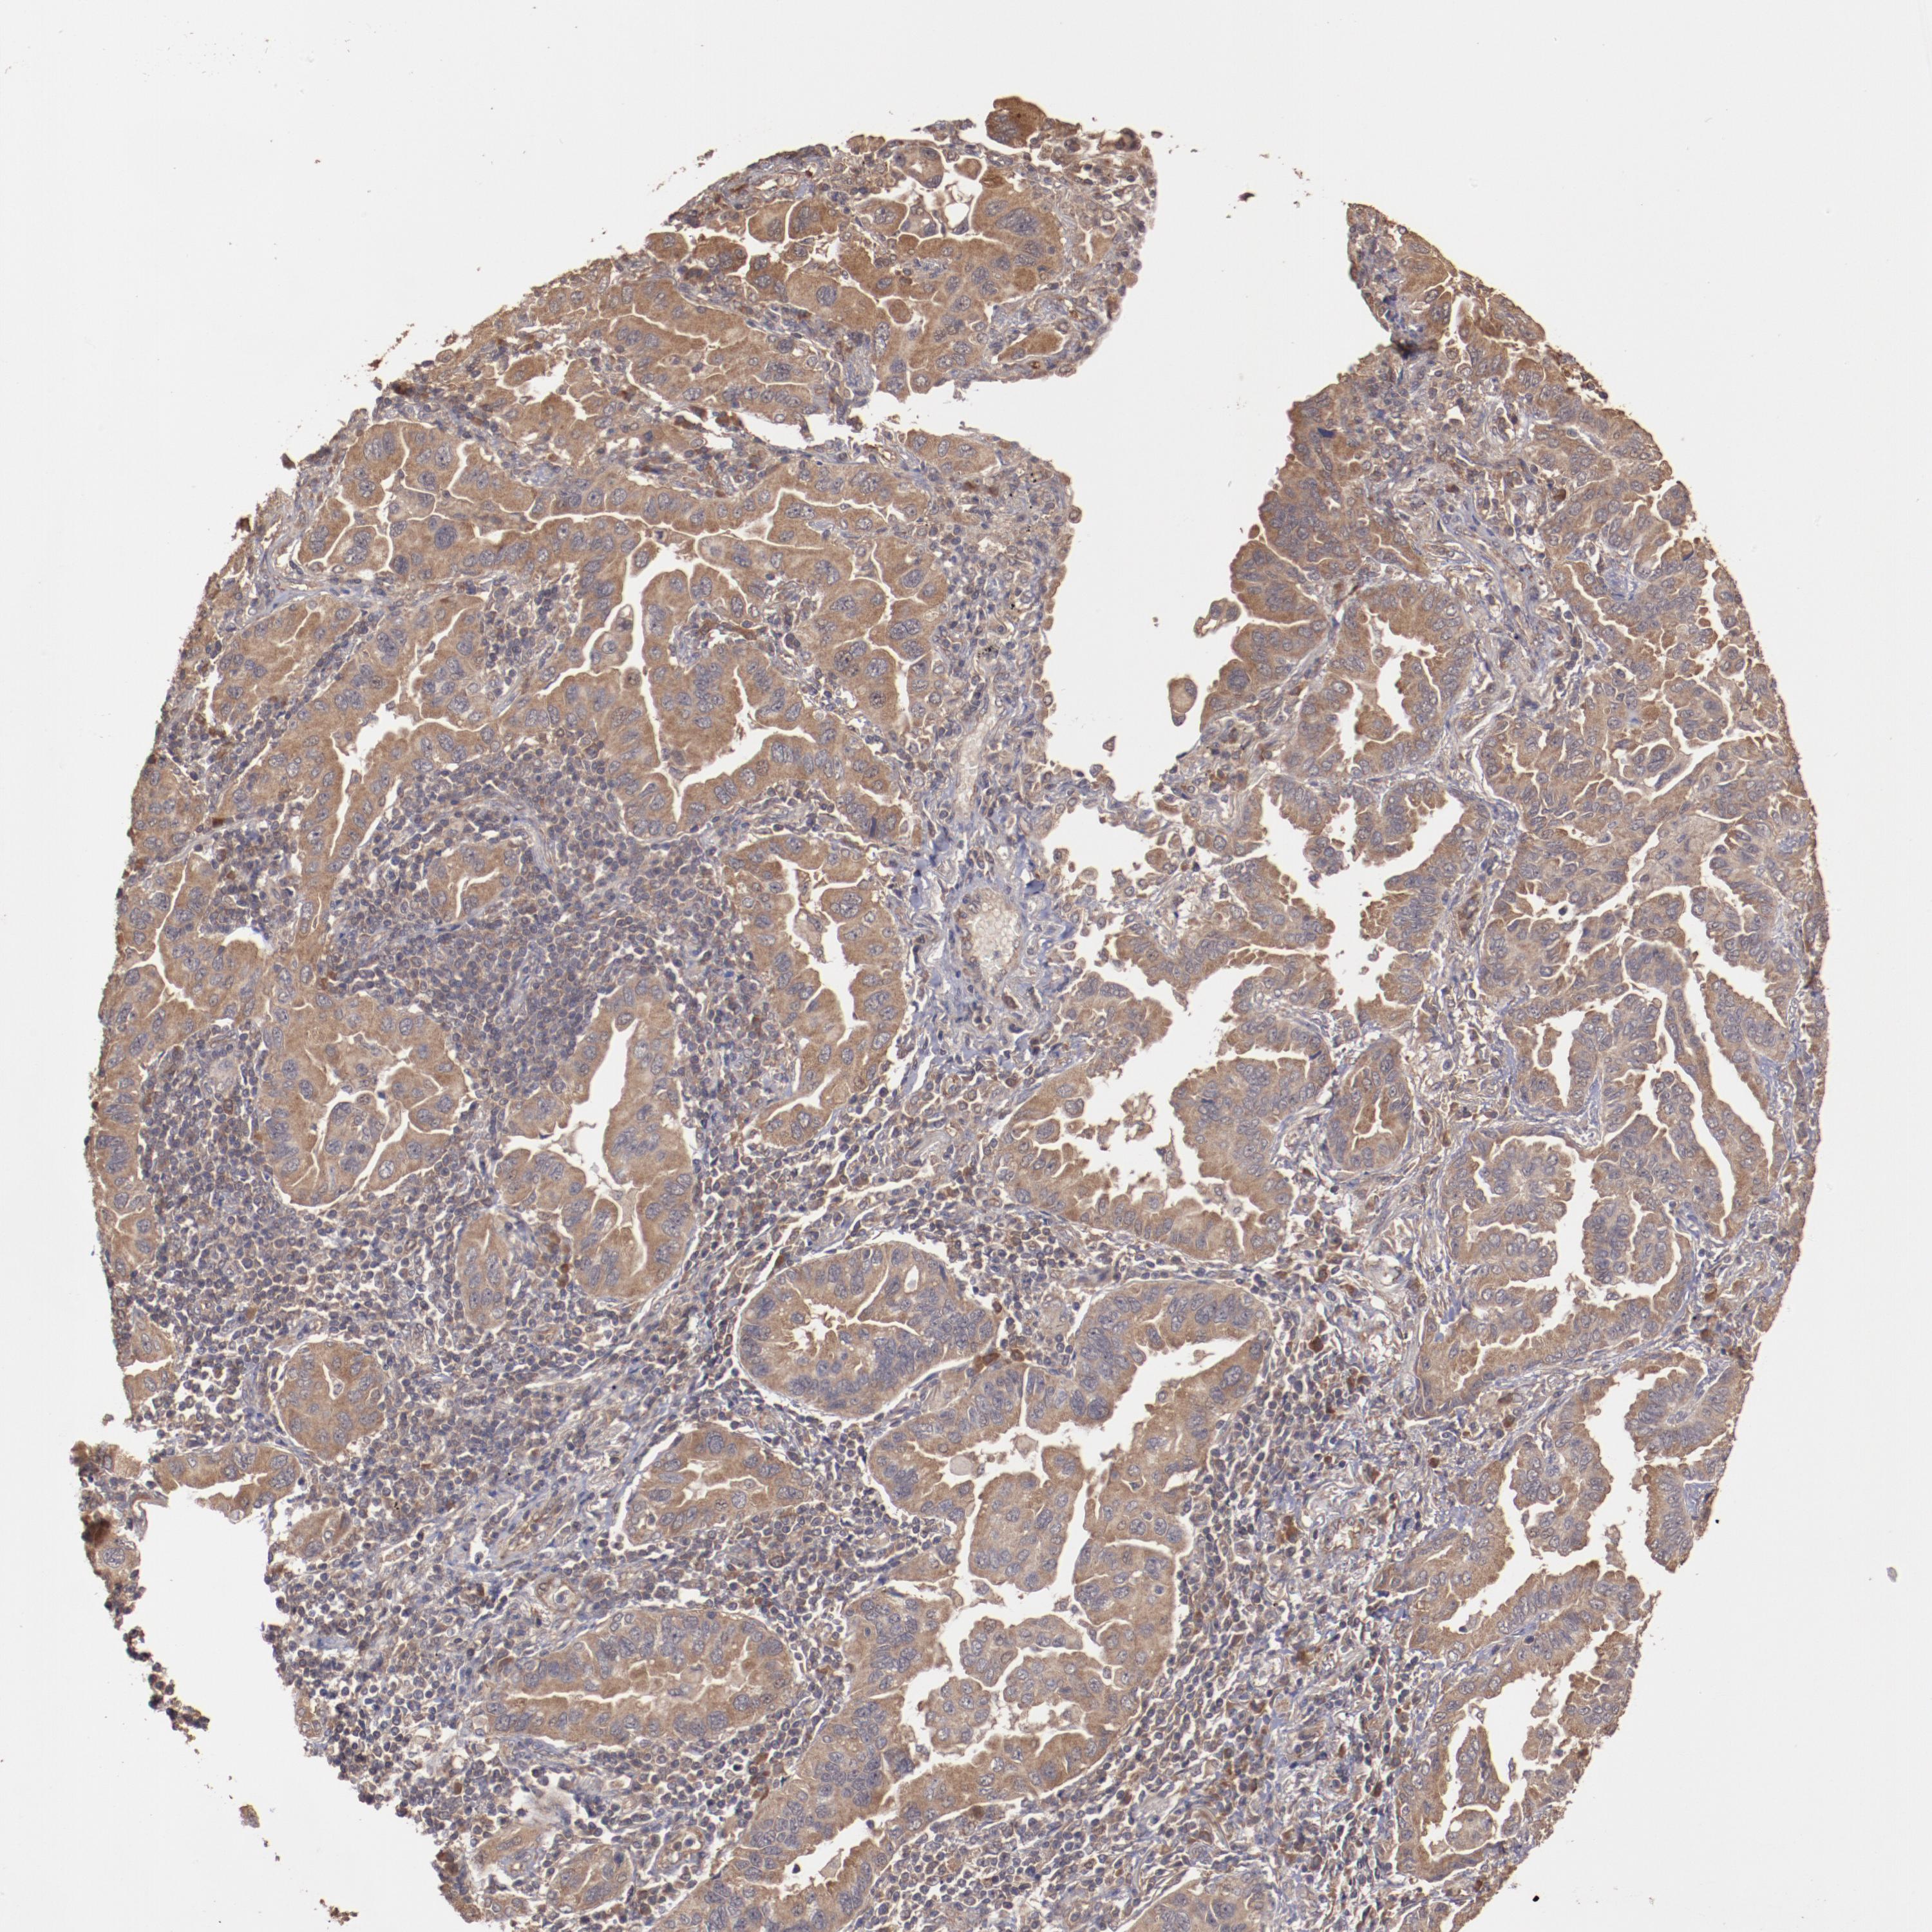

CANCER LUNG CANCER Show tissue menu

Lung cancer

Human cancer